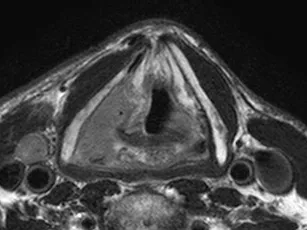

The training will cover all essential topics related to head and neck cancer imaging and will include basic and slightly more advanced knowledge to report. The online course will cover cancers in nasopharynx, oropharynx, oral cavity, hypopharynx and larynx.

Lectures on relevant anatomy, MR and CT technique, tumour staging and follow-up (post-treatment and surveillance) will be followed by individual case readings.